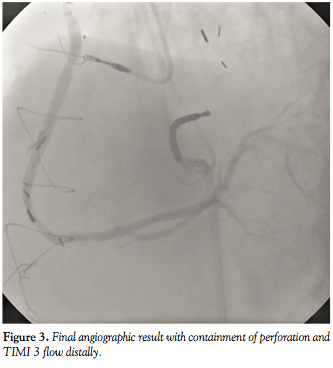

Two overlapping 3.0 x 12 mm Jomed covered stent grafts (Jomed International AB, Helsingborg, Sweden) were deployed over the affected site and subsequent angiography showed TIMI 3 flow with no further extravasation or distal plaque embolization (Figure 3). Bedside echocardiogram revealed a small pericardial effusion posterior to the left atrium and ventricle and no significant fluid around the right ventricle, while the right atrium was not well visualized (Figure 4). Right heart catheterization showed normal right-sided pressures without equalization of diastolic pressures.